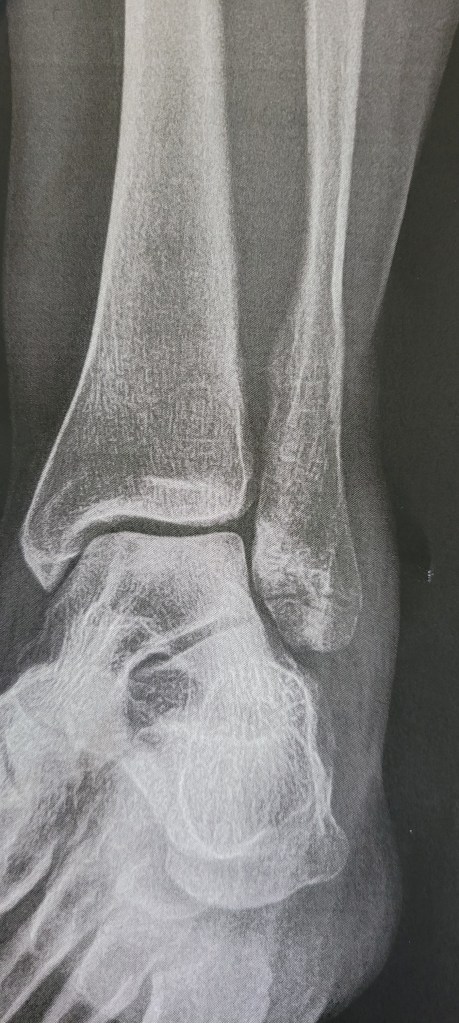

I’m at daughter’s house now in preparation of going to doctor tomorrow. She fell on a walnut while walking to rowing class and broke her foot (her fibula) see photo.